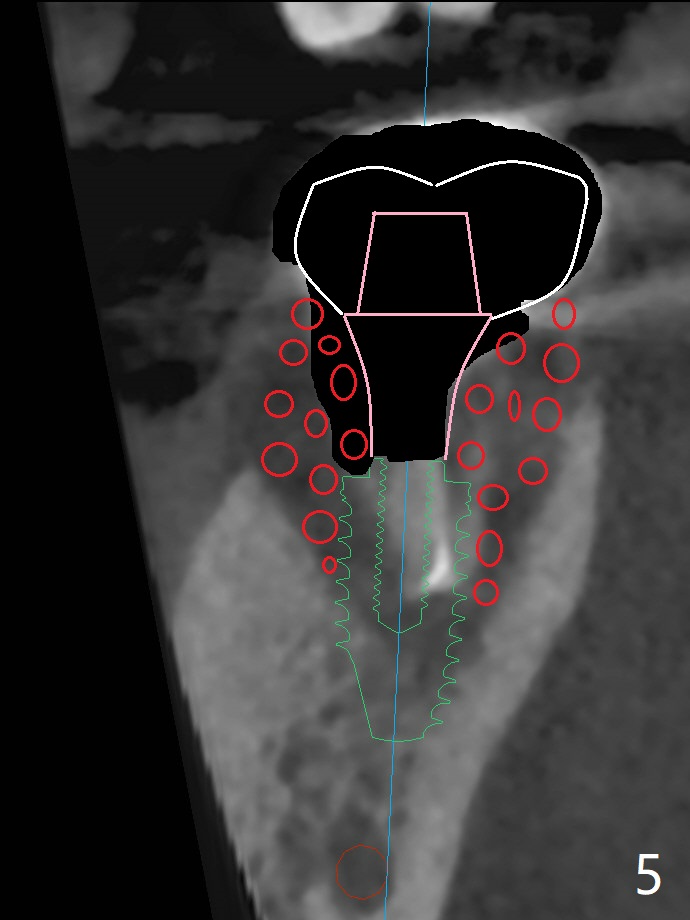

34岁男抱怨右下7根管治疗后牙齿松动,根尖片证实根裂(图一),第二前磨牙和第一磨牙之间有致密骨质(图一:*,图三)。尽管患牙周围骨质吸收严重,尤其是颊侧牙槽嵴(图二:B),必须做即刻种植。植骨有时效果不佳,没有减少手术难度。拖延治疗可能增加对合牙过度萌出,尤其是咬合力大病人。虽然植体颊侧螺纹有暴露危险(图四:>),但是颊侧牙龈附着很长(双箭头),结合基台(图五:粉红色)和临时牙冠(白色),牙龈创造有利的植骨床(红色:骨粉)。